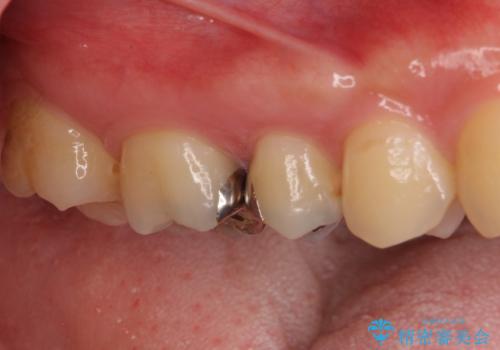

- 奥歯の銀歯の下にあるむし歯治療を希望して来院された患者様です。

口を開けたときに見えてしまう部分はセラミックインレーやジルコニアクラウンに、目立たない部分はゴールドインレーにてむし歯治療を行うこととしました。

機能面を優先すると、PGAインレー(ゴールドインレー)による修復治療やPGAクラウンによる補綴治療が望ましいのですが、笑ったときに見えている銀歯がどうしても気なってしまうとのことで、目立ってしまう奥歯はセラミックインレーやセラミッククラウンを装着することとしました。